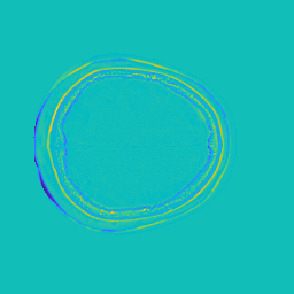

Model-based treatment planning for transcranial ultrasound therapy typically involves mapping the acoustic properties of the skull from an x-ray computed tomography (CT) image of the head. Here, three methods for generating pseudo-CT images from magnetic resonance (MR) images were compared as an alternative to CT. A convolutional neural network (U-Net) was trained on paired MR-CT images to generate pseudo-CT images from either T1-weighted or zero-echo time (ZTE) MR images (denoted tCT and zCT, respectively). A direct mapping from ZTE to pseudo-CT was also implemented (denoted cCT). When comparing the pseudo-CT and ground truth CT images for the test set, the mean absolute error was 133, 83, and 145 Hounsfield units (HU) across the whole head, and 398, 222, and 336 HU within the skull for the tCT, zCT, and cCT images, respectively. Ultrasound simulations were also performed using the generated pseudo-CT images and compared to simulations based on CT. An annular array transducer was used targeting the visual or motor cortex. The mean differences in the simulated focal pressure, focal position, and focal volume were 9.9%, 1.5 mm, and 15.1% for simulations based on the tCT images, 5.7%, 0.6 mm, and 5.7% for the zCT, and 6.7%, 0.9 mm, and 12.1% for the cCT. The improved results for images mapped from ZTE highlight the advantage of using imaging sequences which improve contrast of the skull bone. Overall, these results demonstrate that acoustic simulations based on MR images can give comparable accuracy to those based on CT.